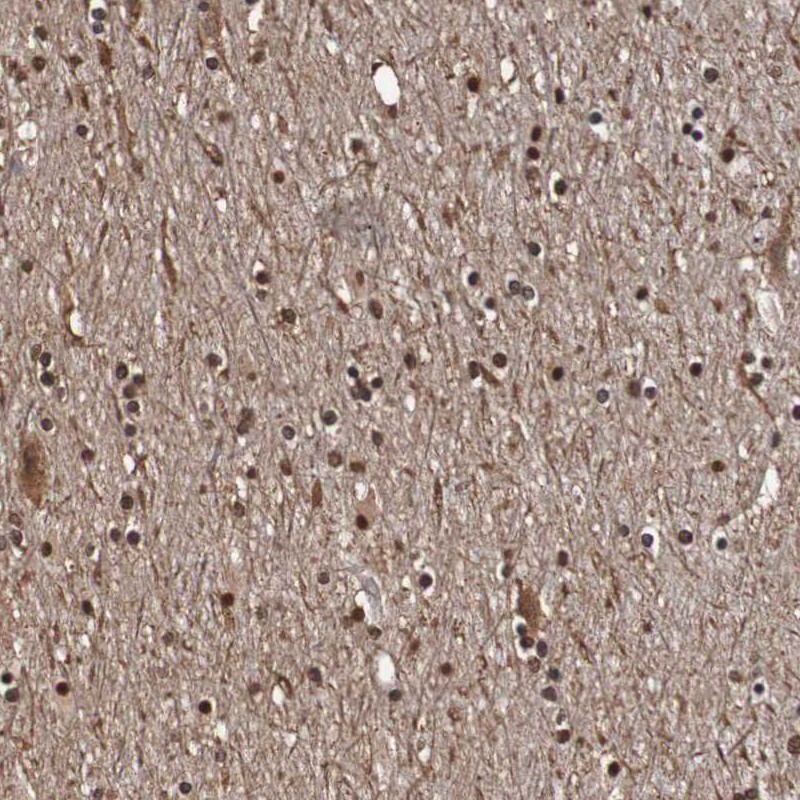

Immunohistochemistry analysis in human cerebral cortex and pancreas tissues using Anti-SEZ6 antibody. Corresponding SEZ6 RNA-seq data are presented for the same tissues.